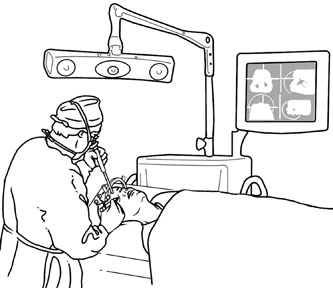

the retracted lateral rectus muscle. Deep orbital dissection requires

fiberoptic illumination and loupe magnification at a minimum, and often

it is best performed with the operating microscope to aid in identification

of the vital vascular and neural structures within the orbit. After removal or biopsy of the proposed lesion, the orbital rim is reinserted